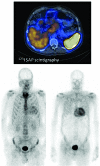

Light chain amyloidosis is the most common type of amyloidosis as a consequence of protein misfolding of aggregates composed of amyloid fibrils. The clinical features are dependent on the organs involved, typically cardiac, renal, hepatic, peripheral and autonomic neuropathy and soft tissue. A tissue biopsy or fat aspirate is needed to confirm the presence/type of amyloid and prognostic tools are important in a risk stratified approach to treatment. Autologous stem cell transplant eligibility should be assessed at baseline, weighing the reversible or non-reversible contraindications, toxicity of treatment and chemotherapy alternatives available. Chemotherapy options include melphalan, thalidomide, bortezomib, lenalidomide, bendamustine in combination with dexamethasone. Many studies have explored these treatment modalities, with ongoing debate about the optimal first line and sequential treatment thereafter. Attaining a very good partial response or better is the treatment goal coupled with early assessment central to optimizing treatment. One major challenge remains increasing the awareness of this disease, frequently diagnosed late as the presenting symptoms mimic many other medical conditions. This review focuses on the treatments for light chain amyloidosis, how these treatments have evolved over the years, improved patient risk stratification, toxicities encountered and future directions.